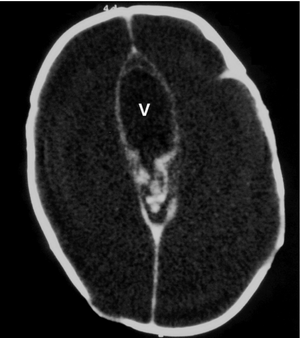

Hydranencephaly-dilated third ventricle (V) with absent thalami and basal ganglia and cerebral cortex